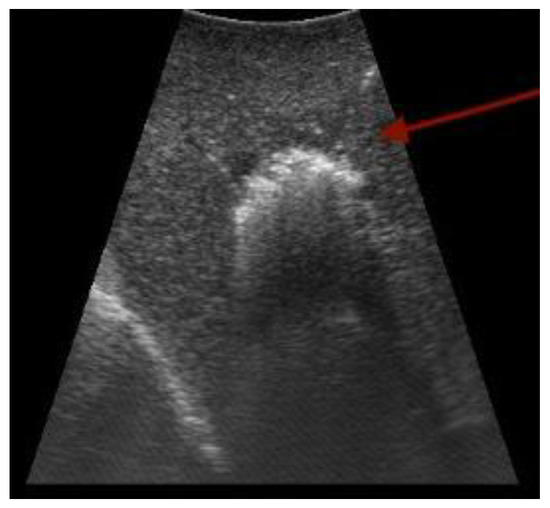

3.1. Ultrasound

- Bartos, A.; Iancu, I.; Ciobanu, L.; Badea, R.; Sparchez, Z.; Bartos, D.M. Intraoperative ultrasound in liver and pancreatic surgery. Med. Ultrason. 2021, 23, 319–328. [Google Scholar] [CrossRef] [PubMed]

- van der Steen, K.; Bosscha, K.; Lips, D.J. The value of laparoscopic intraoperative ultrasound of the liver by the surgeon. Ann. Laparosc. Endosc. Surg. 2021, 6, 17. [Google Scholar] [CrossRef]